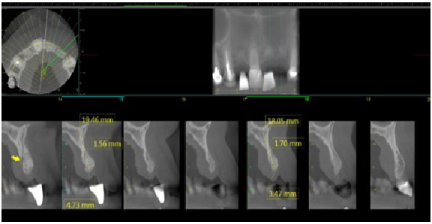

Four months later a new CBCT of the maxillary arch was completed and at all sites, #s 7. 9, and 10 with successful GBR achieved and implant placement was planned using the Anatomage (San Jose, CA, USA) implant planning software (Figures 17, Figure 18, and Figure 19). Each site went from less than 2 mm of width preoperatively to a width of 7 mm four month after grafting.

Figure 17: Post-op four months grafting #7 site CBCT and Anatomage implant planned. Notice the increased bone width from a preoperative width of less than 2 mm to a width greater than 6 mm. View Figure 17

Figure 18: Post-op four months grafting #9 site CBCT and Anatomage implant planned. Notice the increased bone width from less than 2 mm to 7 mm. View Figure 18

Figure 19:Post-op four months grafting #10 site CBCT and Anatomage implant planned. Notice the increased bone width from a preoperative width of less than 2 mm to a width after 4 months of 7 mm. View Figure 19